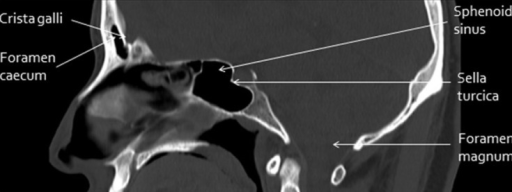

Ct is the modality of choice in defining the bony anatomy of the skull base and to depict the thin cortical margins of skull base neurovascular foramina. An interactive program for learning skull base anatomy welcome to navigating the skull base.

Ct skull base anatomy. You can however go directly to any section using the links below. B axial ct image with color coded overlay shows the skull base bones. The skull base can be evaluated by computed tomography ct which will demonstrate the bony structures of the skull base with its foramina and fissures for vessels and cranial nerves the temporal bone and sinonasal cavities.

Ct anatomy of skull base. Blue central skull base csb purple posterior skull base teal anterior skull base asb. Foramina of the skull base and the structures that pass through them.

Cranial foramina for further details. A axial three dimensional reconstructed ct image with color coded overlay shows the skull base sections. Ct anatomy of skull base.

The base of the skull is perforated by numerous foramina which allow vessels and nerves to pass through the base of the skull allowing the intracranial cavity to communicate with the rest of the body see main article. Skull ct anatomy the sagittal suture is the line where the right and left parietal bone are in contact. A noncontrast sinus or skull base ct which covers the mastoids temporal bone and entire skull base is recommended and intravenous contrast is not usually necessary as the mri will provide soft tissue detail.

Ct is more sensitive in detecting fibro osseous skull base lesions calcification and sclerosis. The module interface is meant to mimic a radiology workstation with adjacent image scrolling via arrow keys and or mouse wheel button. Navigating the skull base identify the petro occipital fissure to navigate the major structures of the skull base.